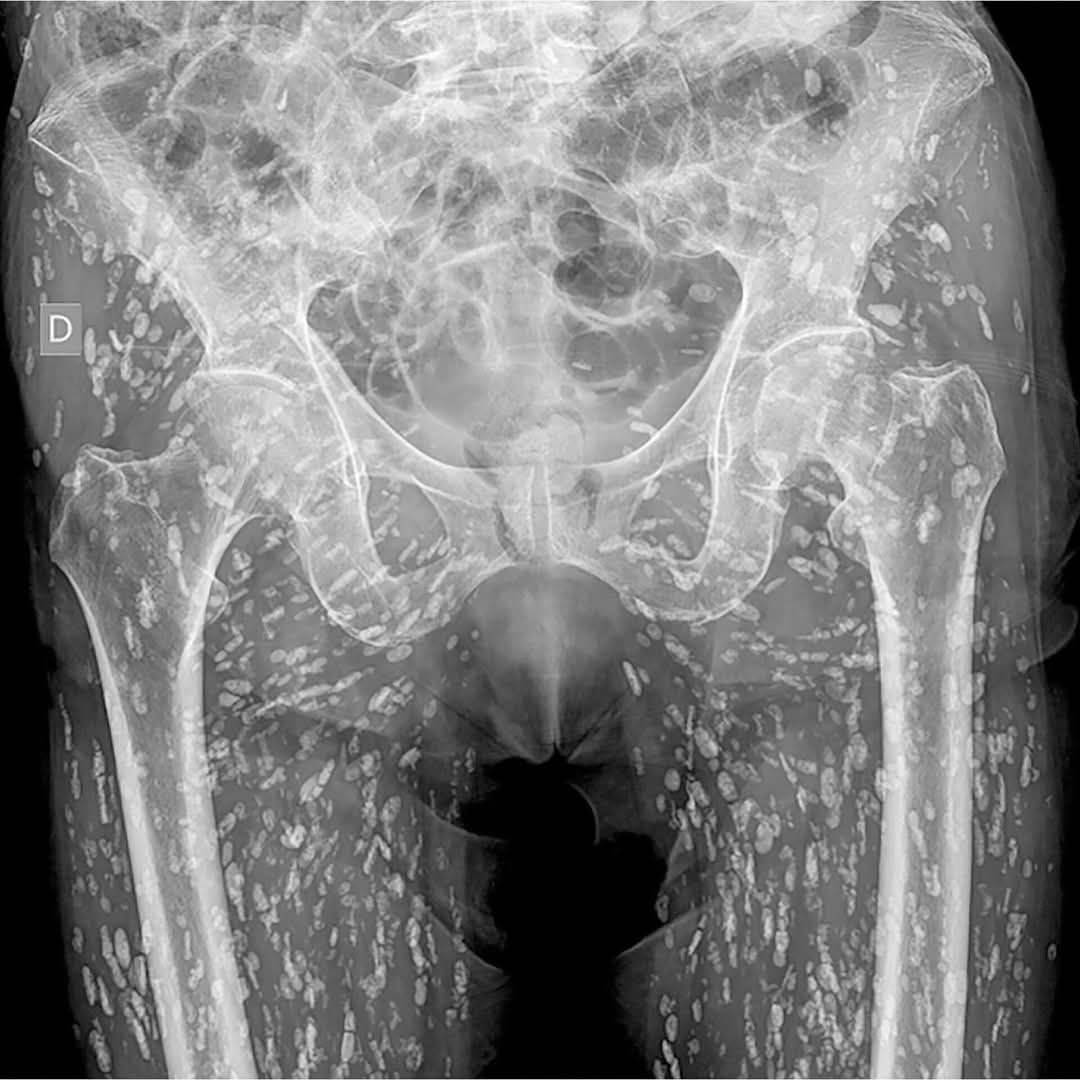

根據媒體《Khaosod》的報導,一名泰國網友「Ai Jaeo Mueang Chan」在臉書分享,自己過去在擔任X光助理時,一名婦人到診所拍攝從髖部到腿部的X光,結果影像一出來佈滿詭異陰影,放射科醫師一看,指出這些白點其實全是寄生蟲!他直言,當時的畫面就像下圖:

醫師推測這患者疑似是長期吃生食、生肉,這才間接將寄生蟲的蟲卵或幼蟲吃下肚。在場醫護人員聽了全都嚇傻,看著全身都是寄生蟲的X光,有人狂起雞皮疙瘩,有人則是不斷用酒精洗手。

事件曝光後,有專家就因此提醒,吃生食有感染絛蟲病的風險,若體內有寄生蟲,恐會出現不斷飢餓、上腹疼痛、腸胃不適、消化不良、噁心嘔吐,腹瀉、便祕、體重減輕等癥狀,避免感染寄生蟲的方法,就是食用肉類要充分煮熟,處理肉類時也要注意衛生、確保生熟食分離,避免交叉感染。